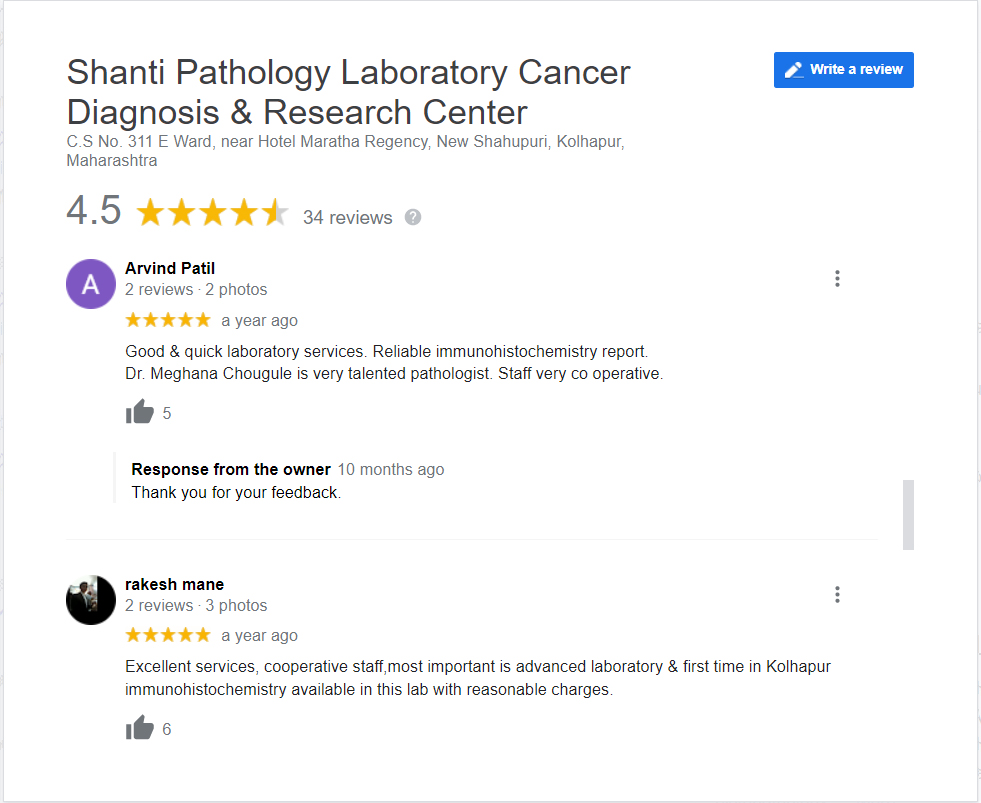

Dr. Meghana Chougule is the chief consultant pathologist at Shanti Pathology Laboratory Cancer Diagnosis & Research Center, Maharashtra.